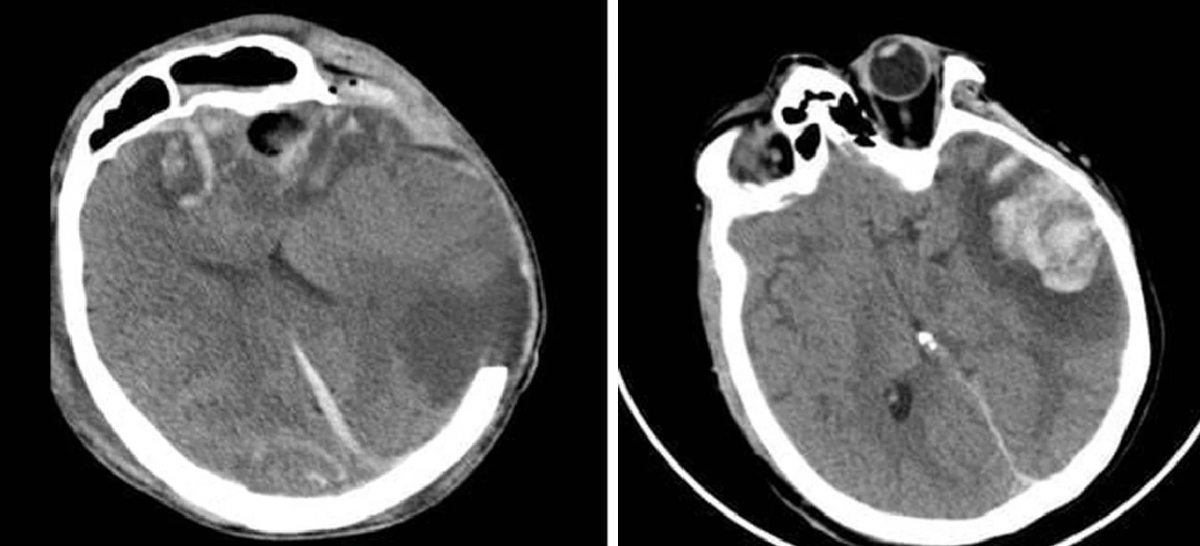

Upon admission, G.A. was in a deep coma, required mechanical ventilation and suffered multiple cerebral haemorrhages with severe brain swelling, doctors said, describing his condition as extremely critical with a high risk of death.

He was placed under intensive care and closely monitored at the hospital’s Surgical Intensive Care Unit. After more than 10 days of intensive treatment, the patient began to show signs of improvement. By the 20th day, he was successfully weaned off the ventilator, regained spontaneous eye opening and was transferred to the neurosurgery department for further care.

His mother sustained a large temporal brain contusion and showed signs of impaired consciousness. Following medical consultation, doctors opted for conservative treatment. Her condition gradually improved, with recovery of awareness, communication and language function. She was discharged after 10 days of treatment.